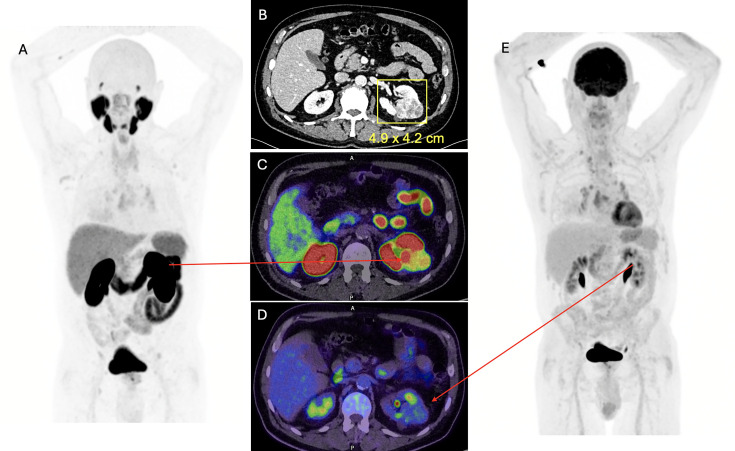

肾细胞癌(RCC)的常规诊断策略主要依赖于超声、CT和MRI。然而,随着几种用于分子成像的新型放射性示踪剂的出现,一种范式正在发生转变。碳酸酐酶IX (CA-IX)成像和sestamibi成像可以帮助识别恶性肾肿瘤,而氟脱氧葡萄糖、前列腺特异性膜抗原和CA-IX示踪剂可以指导RCC的诊断和分期。这些示踪剂可以通过最大限度地减少活检对肾肿块的过度治疗,更好地选择患者进行治疗目的管理,优化低转移性疾病患者的治疗,以及其他新出现的适应症,帮助做出更好的决策。然而,它们都没有被推荐作为标准的临床诊断程序。在这篇综述中,我们探讨了分子影像学检测和分期RCC的最新进展,旨在提高精确诊断和改善患者预后。

Conventional diagnostic strategies for imaging patients with renal cell carcinoma (RCC) have predominantly relied on ultrasonography, CT and MRI. However, a paradigm shift is underway with the emergence of several new radiotracers for molecular imaging. Carbonic anhydrase IX (CA-IX) imaging and sestamibi imaging can assist with identifying malignant renal tumours, whereas fluorodeoxyglucose, prostate-specific membrane antigen and CA-IX tracers can give guidance for diagnosis and staging of RCC. These tracers can assist in enabling better decision-making by minimising overtreatment of renal masses with biopsy, better selecting patients for curative-intented management and optimising treatment for patients with oligo-metastatic disease, among other emerging indications. However, none of them is yet recommended as a standard clinical diagnostic procedure. In this review, we investigate the latest developments in molecular imaging for detecting and staging RCC, aiming to advance precision diagnosis and improve patient outcomes.